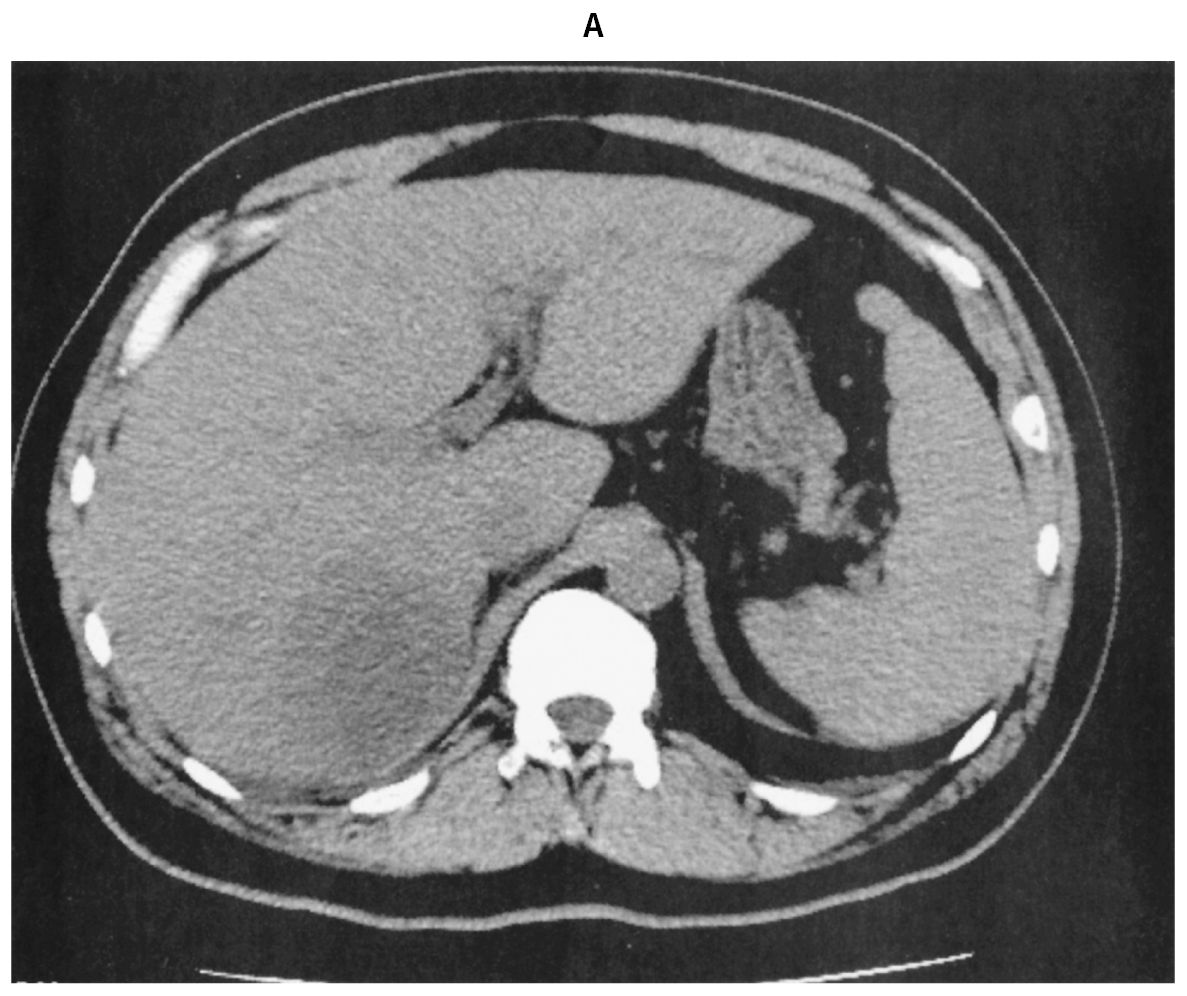

48歳の男性。悪寒と発熱を主訴に来院した。5日前から夕方になると38℃前後の発熱を生じ,軟便が続いていた。本日,悪寒を伴う発熱と両眼の視力低下を認めたため受診した。糖尿病で投薬治療中である。意識は清明。体温38.5℃。脈拍96/分,整。血圧140/74mmHg。呼吸数24/分。SpO2 97%(room air)。眼瞼結膜に異常を認めないが,両側の眼球結膜に充血を認める。頸部リンパ節を触知しない。心音と呼吸音とに異常を認めない。腹部は平坦で,右上腹部に圧痛を認める。右肋骨弓下に肝を3cm触知する。筋性防御と反跳痛は認めない。尿所見:蛋白(-),糖3+,ケトン体(-),潜血(-),沈渣に異常を認めない。血液所見:赤血球450万,Hb 14.0g/dL,Ht 45%,白血球14,600(桿状核好中球30%,分葉核好中球51%,好酸球1%,好塩基球1%,単球5%,リンパ球12%),血小板21万。血液生化学所見:総蛋白7.0g/dL,アルブミン3.5g/dL,総ビリルビン2.0mg/dL,直接ビリルビン1.5mg/dL,AST 35U/L,ALT 35U/L,LD 259U/L(基準124~222),ALP 220U/L(基準38~113),γ-GT 132U/L(基準13~64),アミラーゼ45U/L(基準44~132),CK 157U/L(基準59~248),尿素窒素19mg/dL,クレアチニン1.0mg/dL,尿酸7.2mg/dL,血糖198mg/dL,HbA1c 6.3%(基準4.9~6.0)。CRP 21mg/dL。胸部エックス線写真に異常を認めない。腹部単純CT(A)と腹部造影CT(B)とを下に示す。